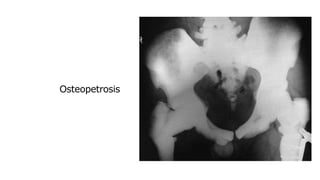

Generalized increase in bone density

🠶Sclerotic metastases

🠶Osteopetrosis (marble bone disease):

congenital disease.

🠶Myelosclerosis:isa form of myelofibrosis,

replacement of bone marrow by fibrous tissue.

Splenomegally.

Osteopetrosis